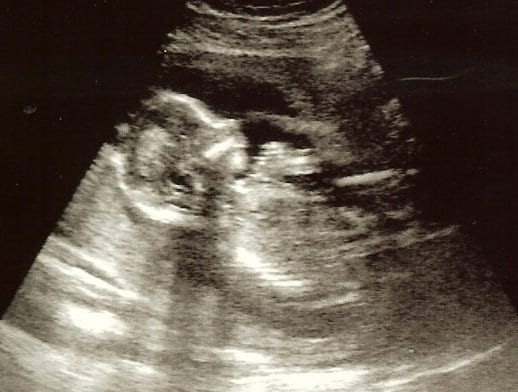

17 haftalık gebelik ve süreçleri